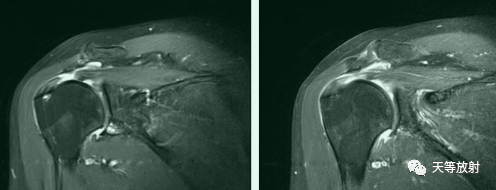

冈上肌完全撕裂

冈上肌全层撕裂伴肩撞(骨赘形成)

冈上肌全层撕裂MRI间接关节造影表现

冈上下肌撕裂